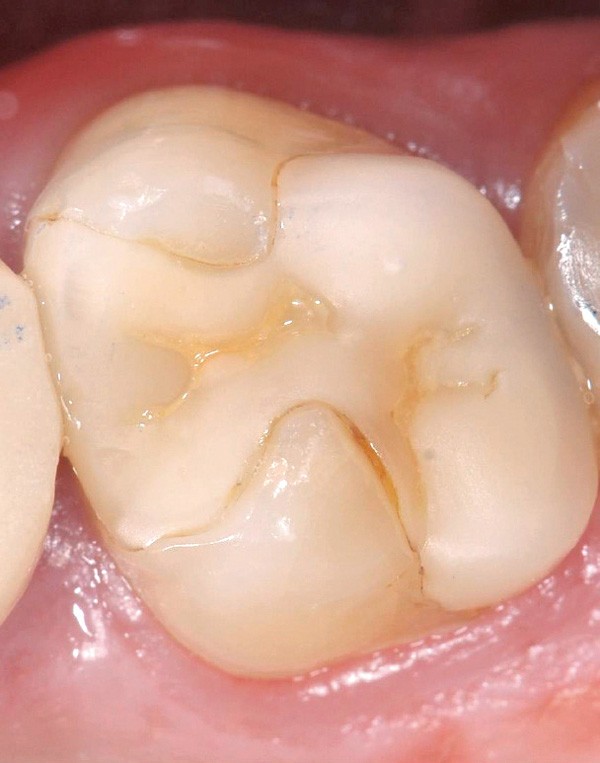

L’omnipraticien est très souvent confronté à cette question lors de sa pratique quotidienne : quel est le bon moment pour adresser les enfants chez l’orthodontiste ? La réponse peut recéler quelques difficultés, car elle est spécifique à chaque enfant. Le temps où il était conseillé d’attendre la denture définitive pour intervenir est révolu : certaines interventions précoces permettent aujourd’hui dans certains cas de raccourcir et de simplifier les traitements orthodontiques. C’est notamment le cas des anomalies transversales, qui sont celles qui sont traitées le plus précocement, dès 6 ans. Ainsi, lors d’anomalie cliniquement évidente, la consultation orthodontique s’impose. Cependant, certaines anomalies sont plus discrètes, et donc plus difficiles à dépister. Une panoramique doit toujours être réalisée en première intention afin de dépister les agénésies. Puis, même en l’absence d’anomalie évidente, il est recommandé d’adresser les enfants chez l’orthodontiste entre 7 et 9 ans : celui-ci sera ainsi à même d’adapter la prise en charge, et surtout l’âge idéal de prise en charge pour chaque patient(fig. 3 et 4).